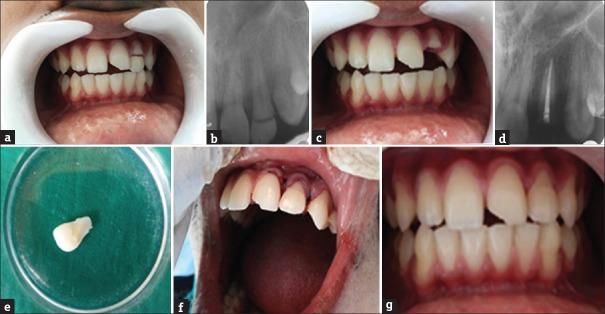

Reattachment of the tooth fragment is an ultraconservative technique for managing coronal tooth fractures when the tooth fragment is available, and there is minimal violation of the biological width. The advances in adhesive dentistry have allowed dentists to use the patient's own fragment to restore the fractured tooth which provides fast and esthetically pleasing results. This article reports fragment reattachment technique and presents two clinical cases of complicated crown fracture.

当牙碎片可用且对生物学宽度的侵犯最小时,牙碎片再附着是治疗冠部牙折的一种超保守技术。牙体粘接修复技术的进步使牙医能够使用患者自身的碎片来修复折断的牙齿,从而提供快速且美观的效果。本文报道了碎片再附着技术,并展示了两例复杂冠折的临床病例。